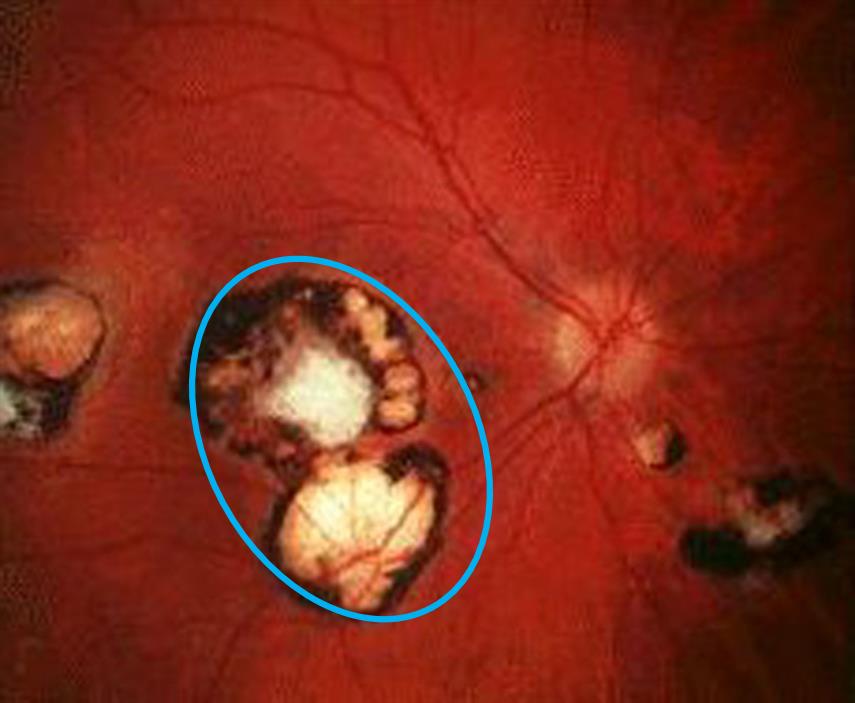

Figure/Illustration A is a depiction of a retinal exam demonstrating macular lesions (blue circle) consistent with chorioretinitis. This finding is classically seen in patients with congenital toxoplasmosis infection.

This infant with a purpuric rash, chorioretinitis, signs of hydrocephalus, and diffuse intracranial calcifications most likely has congenital toxoplasmosis infection.

Toxoplasmosis is a classic "TORCH" infection that is transmitted via the consumption of undercooked meat, ingestion of contaminated cat feces, or consumption of unpasteurized goat’s milk. Maternal toxoplasmosis infection is usually asymptomatic but may present with generalized symptoms such as low-grade fever and lymphadenopathy. Primary transplacental transmission occurs when the mother is infected, usually after the first trimester. Infants with congenital toxoplasmosis classically present with the triad of chorioretinitis, intracranial calcifications, and hydrocephalus. Signs of hydrocephalus include lethargy, vomiting, seizures, enlarged head circumference, and ventriculomegaly. Jaundice, sensorineural hearing loss, low birth weight, hepatosplenomegaly, and a “blueberry muffin rash” may also be seen. Treatment includes pyrimethamine and sulfadiazine, along with folinic acid to prevent bone marrow suppression.